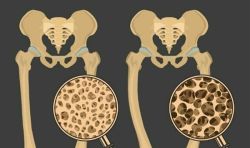

Loãng xương và thiếu xương đều là những vấn đề về xương. Sự khác biệt giữa hai tình trạng này là ở mức độ giảm mật độ xương. Cùng tìm hiểu về sự khác biệt giữa loãng xương và thiếu xương, ai có nguy cơ mắc phải cũng như những bước cần thực hiện để bảo vệ sức khỏe xương.

Khi tốc độ mất khoáng chất trong xương nhanh hơn tốc độ tái tạo thì được gọi là khử khoáng xương. Điều này có thể dẫn đến các vấn đề khác, bao gồm cả bệnh loãng xương.